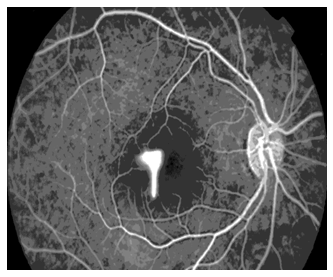

Arteriovenous phase: (Figure 9) The dye completely fills the lumen of the vein. Perifoveal capillary network is best visualized at 20 to 25 seconds after the injection of the dye when the concentration of the dye is maximum The fovea appears hypo fluorescent because of the absence of the blood vessels in the foveal avascular zone (FAZ) and due to the blockage of the background choroidal fluorescence by the increased pigment in the tall RPE cells at the fovea (Figure 10).

Figure 9 Arteriovenous phase.

Figure 10 RPE cells at the fovea.